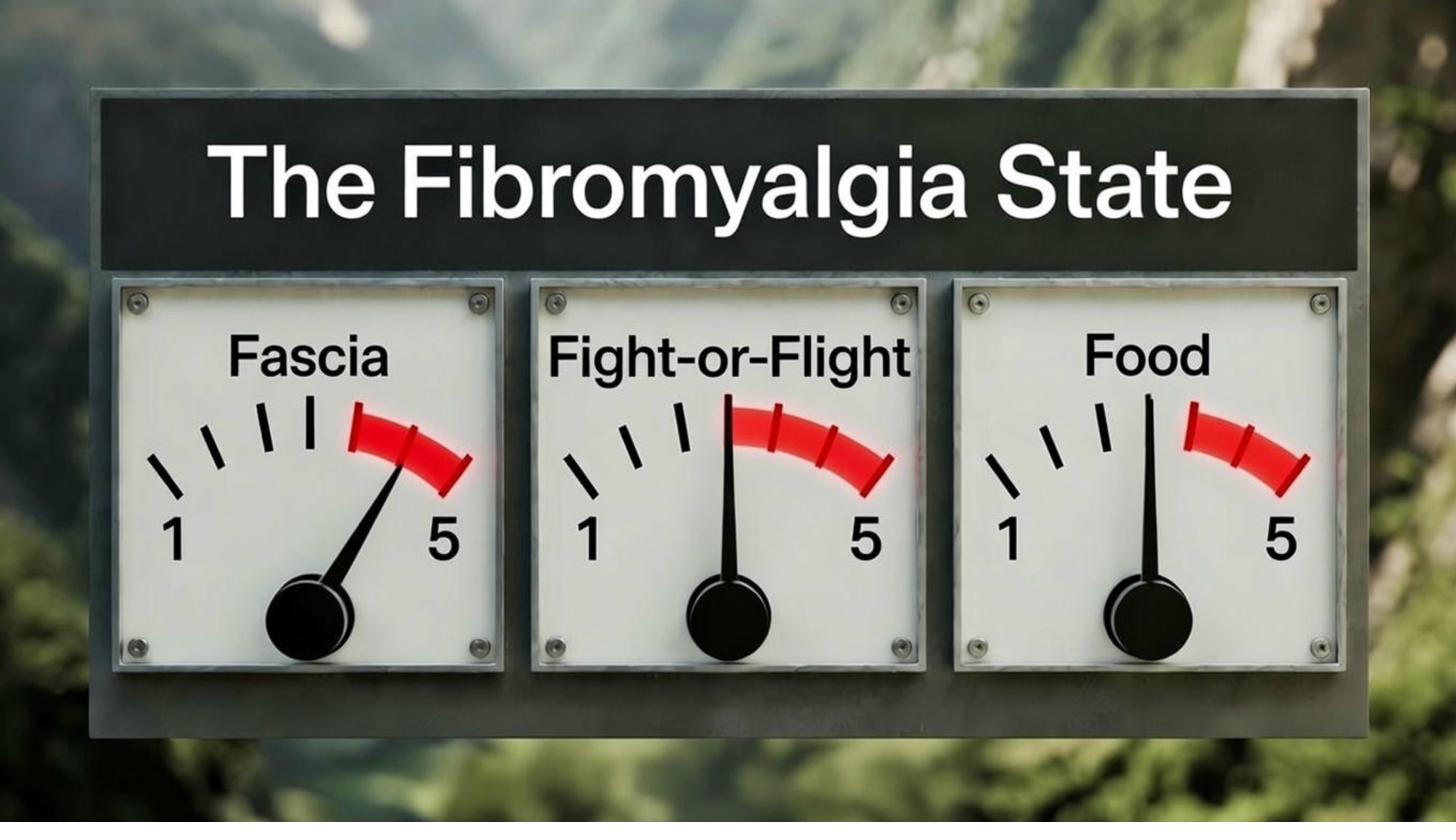

We began to see a pattern. Three key elements kept showing up in every case where people were stuck in that state. Three key systems of the body were always involved.

The research and knowledge exists on all three, but no one has pieced them together as we have. The way these three systems interact with each other unlocked the door to understanding your Fibromyalgia pain.

When any one of them is pushed too far, your body could usually still cope. But when all three are turned up high at the same time, you cross an invisible line and enter the State of Fibromyalgia.

What Affects Your Dials?

Let's take a deeper look at the three dials that shift you into your state of Fibromyalgia, to help you understand how and why they send you into pain, what your flare-ups really are, and how to control the dials to bring you back to pain free.

In Summary: The 3 Systems That Dial You Into the State of Fibromyalgia

Take a moment and let this sink in.

You've just seen the three dials laid out clearly: Fascia, Fight-or-Flight, and Food. Each one backed by solid research, each one playing its part in the State of Fibromyalgia. The real perspective shift happens when you realise these systems interlink and affect each other.

Fascia is the main driver but it never works alone.

The moment Fascia sends those danger signals, your Fight-or-Flight system hears them loud and clear. It responds exactly as it's meant to, by tightening muscles, raising stress hormones, and keeping you in a low-level state of alert. That tightness feeds straight back into the Fascia, making restrictions worse. Simultaneously, the chronic stress disrupts your gut microbiome, triggering inflammation that circles right back to stiffen Fascia even more.

All three systems interlink and affect each other simultaneously, in real time. Raise one, and the others follow. Lower one, especially Fascia, and the others naturally begin to calm. This is where the medical industry gets stuck.